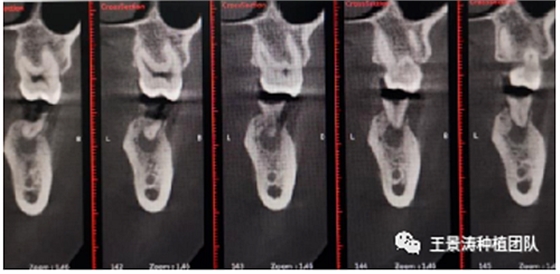

其次初期穩(wěn)定性的獲得,前牙美學(xué)區(qū)種植體的初期穩(wěn)定性主要是依靠腭舌側(cè)骨板及基底骨來獲得的。后牙區(qū)的穩(wěn)定性主要依靠多根牙的牙槽間隔及根尖到重要解剖位置的高度的骨質(zhì)獲得(主要是竇嵴距和管嵴矩的高度,還要參考植入種植體的長度),因此術(shù)前仔細(xì)測量牙槽間隔與根尖至重要解剖結(jié)構(gòu)的高度是后牙即刻種植的關(guān)鍵因素之一。

左側(cè)下頜第二磨牙及右側(cè)下頜第一磨牙同時(shí)即刻種植病例?;颊吣贻p女性,無系統(tǒng)性疾病。37及46殘冠及殘根,且46劈裂,無法冠修復(fù),必須拔除。37根尖慢性炎癥,大量肉芽組織存在,46根分叉較高,根分叉骨質(zhì)尚可。CBCT示:根尖骨質(zhì)至下牙槽神經(jīng)管距離可滿足種植體的初期穩(wěn)定性,遂考慮即刻種植,并在種植體周邊填入骨粉并覆蓋骨膜,雙側(cè)的種植體初期穩(wěn)定性相差無幾,但考慮到37根尖慢性炎癥較大,遂給予埋入式種植。